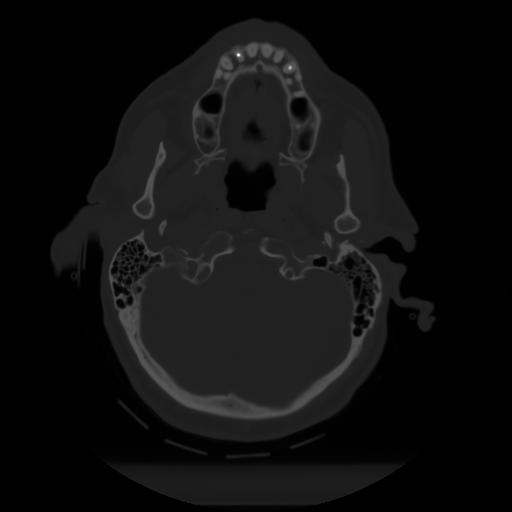

10 P.BLANDAS,,Axial,2.0,P.BLANDAS,,